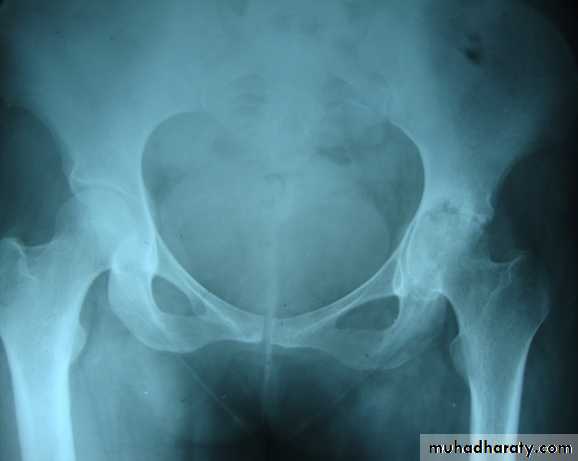

Changes are seen in the feet of diabetics with peripheral neuropathy.A vascular ( a septic ) necrosis :

Avascular necrosis , also known as osteonecrosis , is where there is death of bone due to interruption of the blood supply.The plain radiographic features including :

1. Increase density of the subchondral.

2. crescentic lucent line may be seen just beneath the articular cortex.

3.Articular cartilage space is preserved until degenerative changes super even .

4.In sub capital fracture of the femoral neck & fracture through the waist of the scaphoid bone , the femoral head & proximal pole of the scaphoid become fragmented & dense due to the ischemia .

MRI is imaging modality of choice for demonstrating a vascular necrosis and may show changes at time so early when radiograph may be normal .

A group of conditions , in which no associated cause for a vascular necrosis can be found . But the osteochondritis are now regarded as being due to impaired blood supply associated with repeated trauma .A-Perth's disease :

A vascular necrosis of the femoral head in children , is the most important example of the osteochondritis . the plain radiograph changes :

1.the earliest change is increase in density and flattening of the femoral epiphyses which later on progress to collapse & fragmentation.

2.epiphysis widened & consequently the femoral neck enlarge and may contain small cyst .

3.joint space is widened but the accetabulum not affected .

4.with healing, the femoral head reforms but remain permanently flattened & therefore responsible for OA in later life .